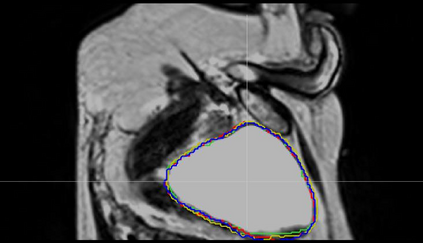

Direct automatic segmentation of objects from 3D medical imaging, such as magnetic resonance (MR) imaging, is challenging as it often involves accurately identifying a number of individual objects with complex geometries within a large volume under investigation. To address these challenges, most deep learning approaches typically enhance their learning capability by substantially increasing the complexity or the number of trainable parameters within their models. Consequently, these models generally require long inference time on standard workstations operating clinical MR systems and are restricted to high-performance computing hardware due to their large memory requirement. Further, to fit 3D dataset through these large models using limited computer memory, trade-off techniques such as patch-wise training are often used which sacrifice the fine-scale geometric information from input images which could be clinically significant for diagnostic purposes. To address these challenges, we present a compact convolutional neural network with a shallow memory footprint to efficiently reduce the number of model parameters required for state-of-art performance. This is critical for practical employment as most clinical environments only have low-end hardware with limited computing power and memory. The proposed network can maintain data integrity by directly processing large full-size 3D input volumes with no patches required and significantly reduces the computational time required for both training and inference. We also propose a novel loss function with extra shape constraint to improve the accuracy for imbalanced classes in 3D MR images.